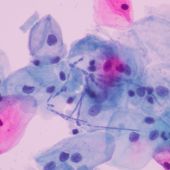

Cell Size

Cell size is crucial in gene and cell therapy as it influences cellular uptake, viability, and therapeutic efficacy. Accurate size measurement ensures optimal cell selection and enhances treatment outcomes.